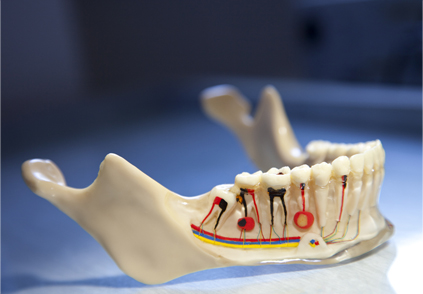

The removal of the infected or irritated nerve tissue that lies within the root of the tooth. It is this infected pulp tissue that causes an eventual abscess.

The first step in a root canal is to obtain access to the nerve. This is accomplished by establishing a small access opening in the top of the tooth. It will be done under a local anesthetic.

The length of the root canal is determined and the infected pulp is removed.

At the same visit, the canal where the nerve is located will be reshaped and prepared to accept a special root canal filling material.

The final step in your root canal will be the sealing of the root canal with a sterile, plastic material called gutta percha. This is done in order to prevent possible future infection.